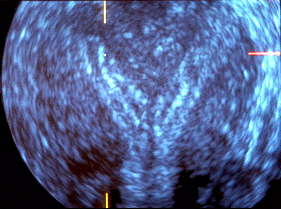

Utérus cloisonné corporéal.